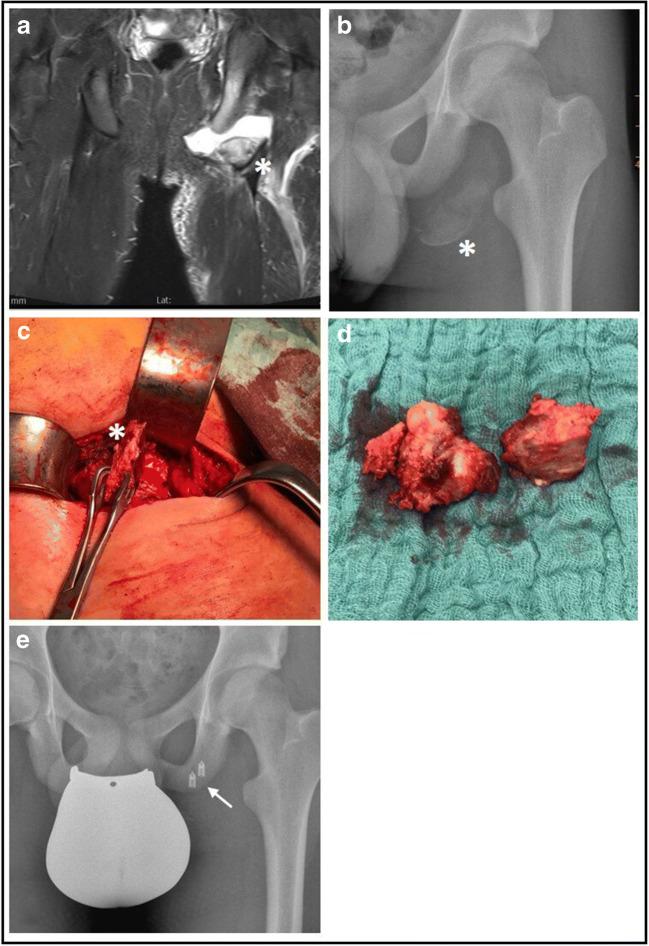

Eleven adolescents with an acute or chronic mean fragment dislocation of 3.3 cm (SD ± 1.7) underwent surgical intervention in the assigned period. The mean post-operative PHAT score was 86.9 (0-100, SD ± 11.9) and thus good to excellent. The majority of adolescents (10/11) was able to return to their pre-injury sports, whereas 63.6% achieved full or nearly full level.

Surgical refixation or restoration of aphoyseal avulsion fractures of the ischial tuberosity result in good to excellent outcomes and return to sport rates, irrespective of the type of intervention. Here prompt diagnosis with a timely intervention seems more promising than delayed interventions in chronic cases. Beyond 1.5 cm of fragment displacement affected patients should be counselled for surgical intervention.